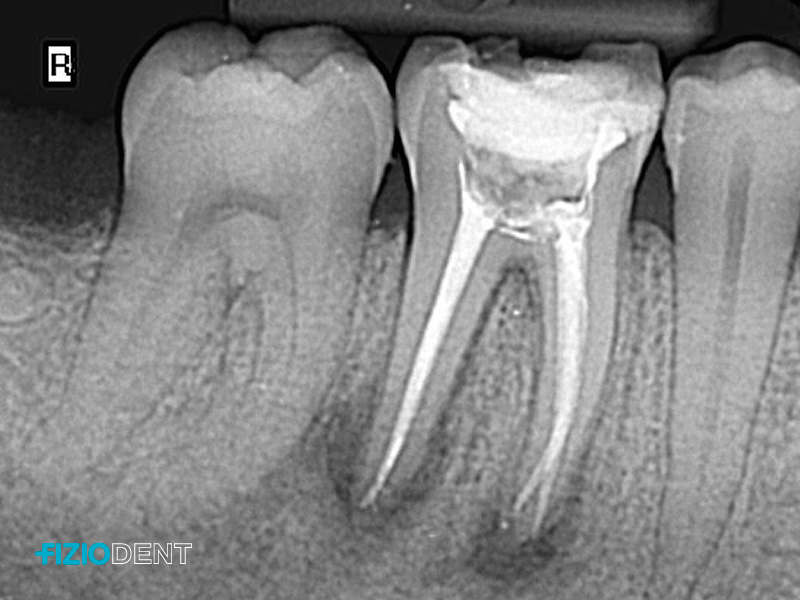

The root canals are filled with a biocompatible material that seals the space and prevents reinfection of the endodontic area.

The success of the endodontic treatment should be checked with an X-ray of the tooth. Ultimately, the tooth should be restored with a filling, post, or crown to ensure proper function and aesthetics.